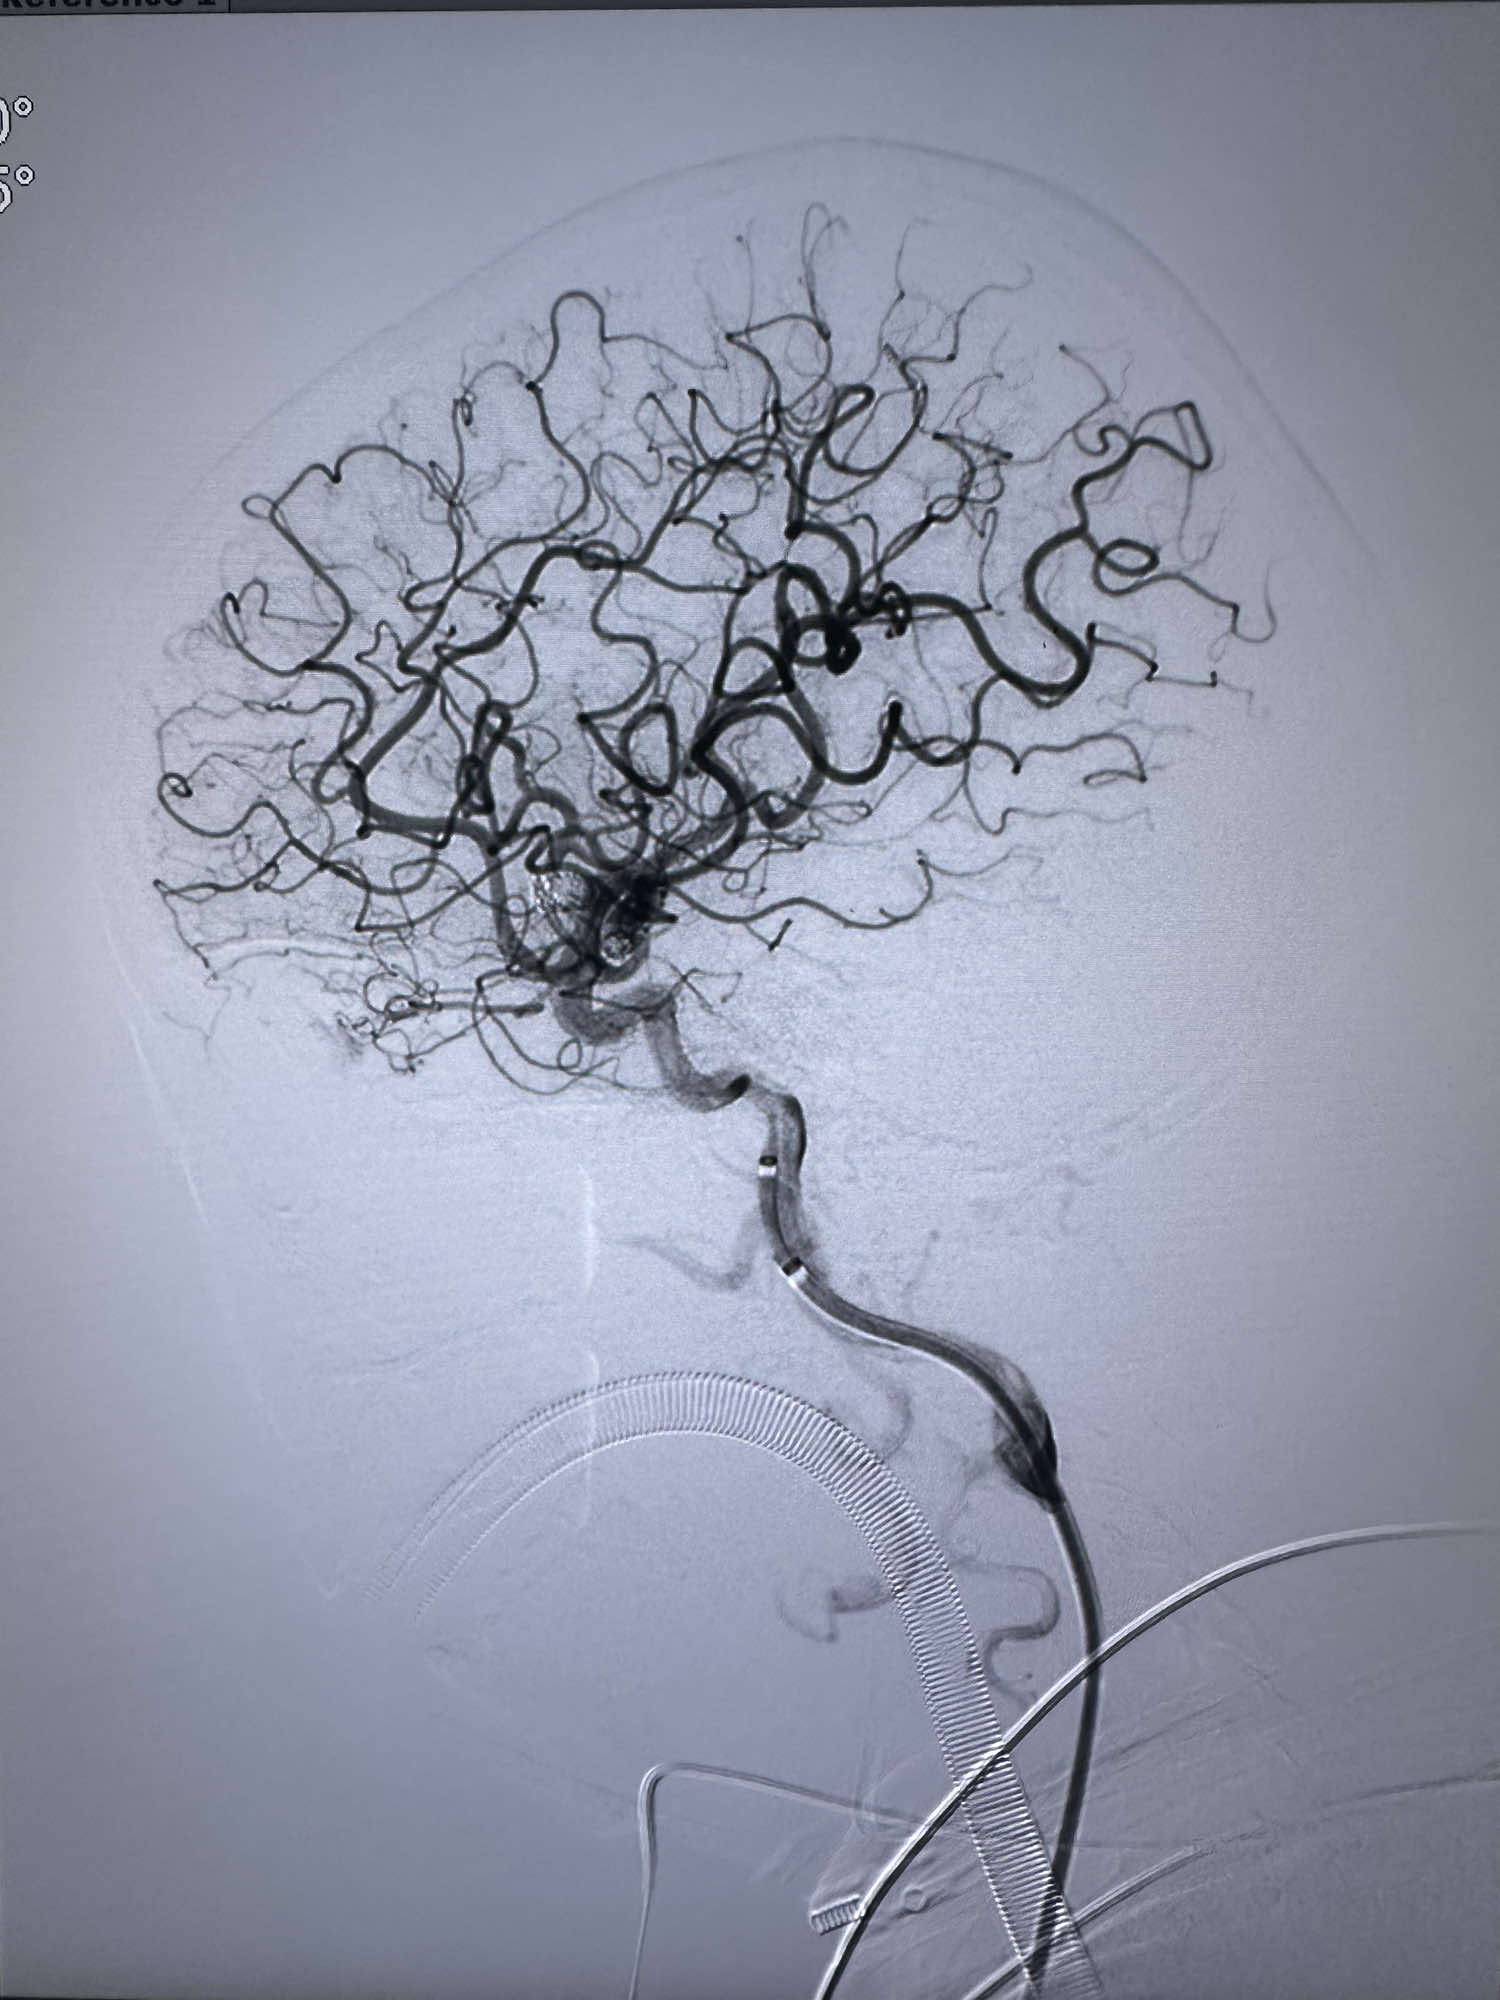

最后造影显示动脉瘤不显影

侧位